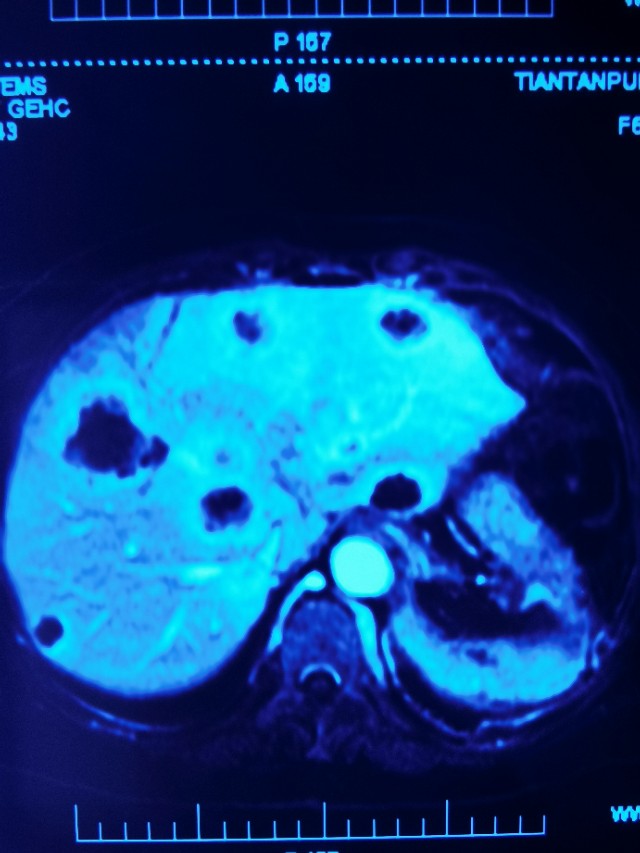

16号术后复查

后两张图是7月份的肝转移瘤HIFU消融后,第一张14号术前检查,15号手术,第二张16号术后复查,总共相差2天。消融效果家属满意,医学同道称赞!